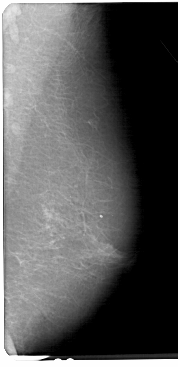

A_1337_1.RIGHT_MLO

RIGHT_CC LINES 5386 PIXELS_PER_LINE 2491 BITS_PER_PIXEL 12 RESOLUTION 43.5 NON_OVERLAY

RIGHT_MLO LINES 5491 PIXELS_PER_LINE 2656 BITS_PER_PIXEL 12 RESOLUTION 43.5 NON_OVERLAY